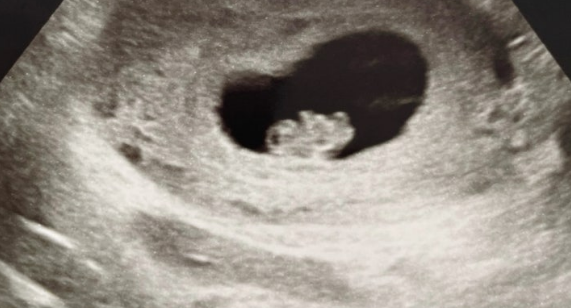

아기의 크기는 약 1.5~2cm 정도로 콩알 수준이지만

자궁은 주먹만 한 크기로 커지고 있어요.